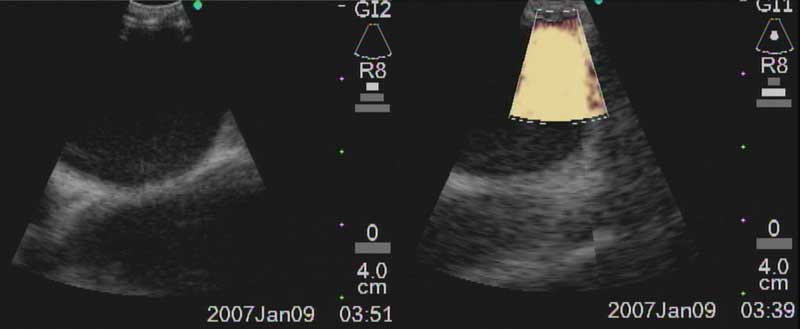

Figure 6a: Ultrasound image of R main pulmonary artery with (right) and without (left) color Doppler.